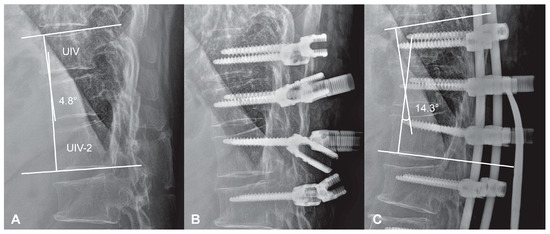

- Screw placement: Pedicle screws were inserted at the UIV, UIV-1, and UIV-2 levels with close attention to sagittal orientation. Screw heads were aligned to accommodate a pre-contoured rod that replicated a mild kyphotic curve, avoiding aggressive anterior angulation.

- Rod contouring and placement: A pre-bent cobalt-chrome rod, shaped to match the intended kyphotic curvature of the TLJ, was positioned across the UIV to UIV-2 levels.

- Controlled distraction: Distraction was sequentially applied between UIV–UIV-1 and UIV-1–UIV-2 using a rod distractor or compressor system. Under radiographic guidance, distraction was adjusted with the goal of producing a segmental kyphosis 5° to 10° greater than the angle measured between UIV and UIV-2 in the prone position. Set screws were progressively tightened during this process to maintain the desired curvature and ensure gradual stress distribution.

- Final locking: After confirming smooth sagittal alignment without abrupt transitions or focal angulation, all screws were securely locked.